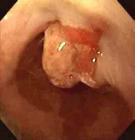

食道癌诊断方法之纤维内窥镜检查:自上个世纪70年代纤维光学镜逐步取代金属硬管镜以来,由于其可弯曲,照明好,视觉广,安全准确,已成为检查上消化道疾病(食管癌、 胃癌等)常规的临床诊断、术后随访、疗效观察的可靠方法。在早期食管癌中,纤维内窥镜的检出率可达85%以上。

(1)早期食管癌的病理形态分型:早期食管癌按其形态可分为隐伏型、糜烂型、斑块型和乳头型。其中以斑块型为最多见,占早期食管癌的 1/ 2左右,此型癌细胞分化较好。糜烂型占 1/ 3左右,癌细胞的分化较差。隐伏型病变最早,均为原位癌,但仅占早期食管癌的1/10左右。乳头型病变较晚,虽癌细胞分化一般较好,但手术所见属原位癌者较少见。

(2)中、晚期食管癌的病理形态分型:可分为髓质型、蕈伞型、溃疡型、缩窄型、腔内型和未定型。其中髓质型恶性程度最高,并占中、晚期食管癌的1/2以上。此型癌肿可侵犯食管壁的各层,并向腔内外扩展,食管周径的全部或大部,以及食管周围结缔组织均可受累,癌细胞分化程度不一。蕈伞型约占中、晚期食管癌的1/6~ 1/ 5,癌瘤多呈圆形或卵圆形肿块,向食管腔内呈蕈伞状突起,可累及食管壁的大部。溃疡型及缩窄型各占中、晚期食管癌的1/10左右。溃疡型表面多有较深的溃疡,出血及转移较早,而发生梗阻较晚。缩窄型呈环形生长,且多累及食管全周,食管粘膜呈向心性收缩,故出现梗阻较早,而出血及转移发生较晚。腔内型比较少见,癌瘤突向食管腔内,呈圆形或卵圆形隆起,有蒂与食管壁相连,其表面常有糜烂或溃疡。肿瘤可侵入肌层,但较上述各型为浅。少数中、晚期食管癌不能归入上述各型者,称为未定型。